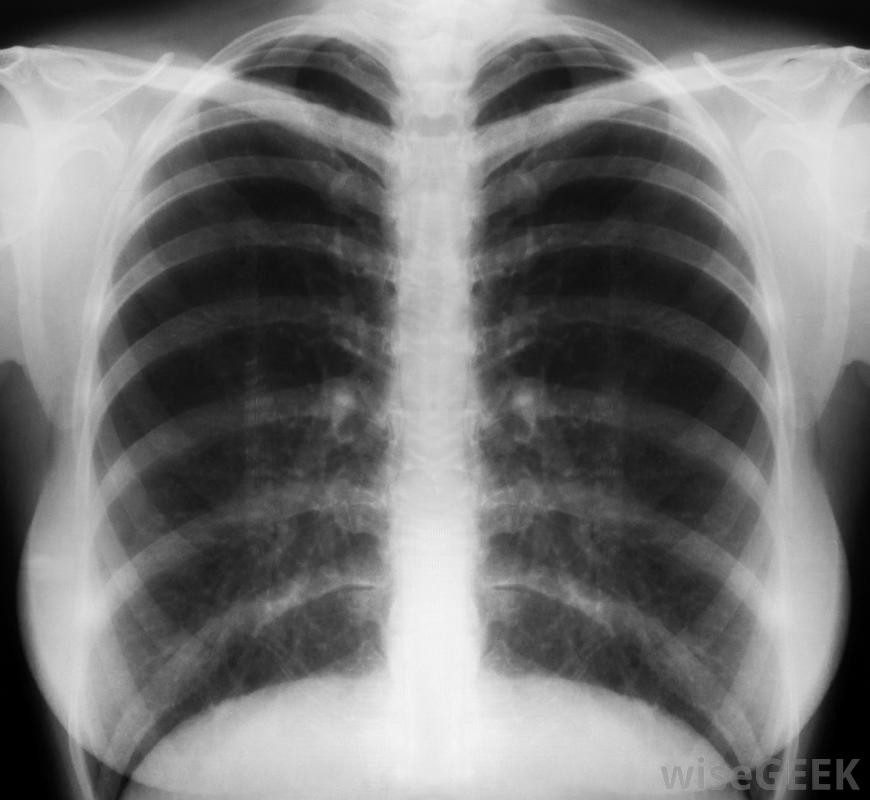

如果怀疑肺部感染或其他损伤,可要求进行胸部x光检查大多数医生建议服用布洛芬,这是一种可以在柜台购买的消炎止痛药。专家建议,这只应该作为一种治疗手段,在进行检查以确定肋骨软骨炎是否是导致胸痛的原因后,健康专家不建议尝试自我诊断这种疼痛,也不建议在进行彻底检查之前进行特定的肋软骨炎治疗在决定肋骨软骨炎的治疗方法之前,医生会检查胸部,同时按压肋软骨关节周围。如果患者在检查时报告该区域疼痛或酸痛,医生通常会诊断这种疼痛是由这种情况引起的。通常只有在检查后才建议对这种情况进行各种治疗。如果怀疑有其他疾病,如肺部感染,或者,如果最近有明显的损伤,医生可能会提供进一步的检查,其中可能包括胸部x光片。当疼痛归因于这些情况之一时,肋软骨炎的治疗也包括治疗潜在的原因。在某些情况下,医生会建议对胸部进行热敷或冷敷以减轻疼痛。在大多数情况下,肋软骨炎的治疗非常少。许多人发现休息几天后疼痛和炎症会自然消失对于一些人来说,症状只出现在剧烈运动期间,并在停止运动后很快消退。在这些情况下,肋软骨炎止痛药治疗可能会帮助那些尽管疼痛仍想继续锻炼的人。